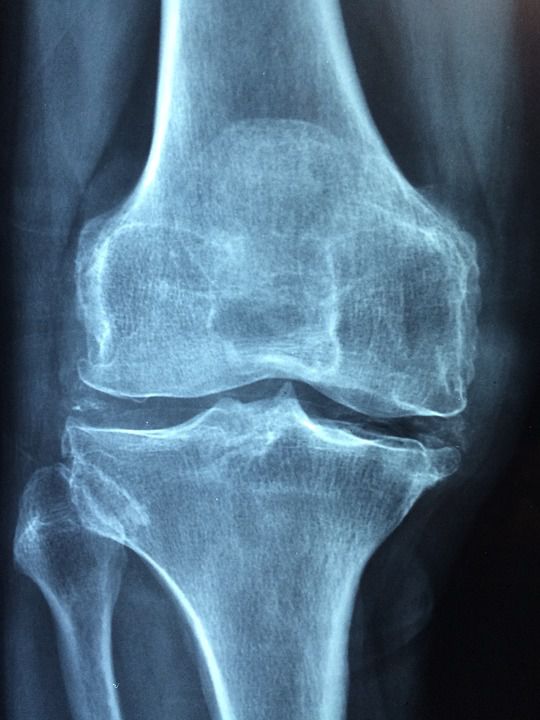

Aprender todo lo que puedas sobre tu afección, incluido el tipo de artritis que tienes y si alguna de tus articulaciones ya está dañada.

Controla tu peso. La obesidad puede empeorar las complicaciones de la artritis y contribuir al dolor que se produce a causa de esta afección. Por lo general, hacer cambios graduales permanentes en el estilo de vida que generen un adelgazamiento progresivo suele ser el método más eficaz para controlar el peso.

Cuando tienes artritis, moverte puede ayudar a disminuir el dolor y la rigidez, mejorar la amplitud de movimiento, fortalecer los músculos, y aumentar la resistencia.